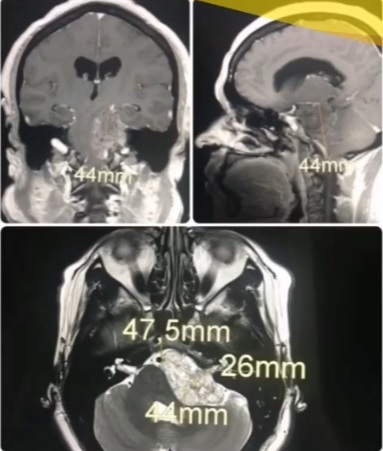

Las hijas de ‘Linda’ Acuña necesitan un millón de pesos para las tres cirugías que necesita su madre para retirar el tumor que ‘asfixia‘ su cerebro.